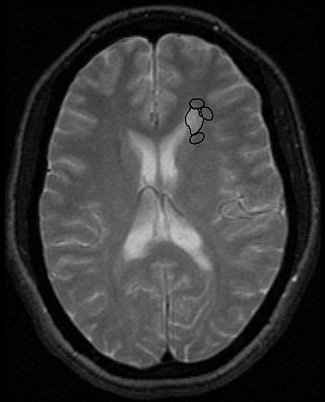

![]() |

| Final area of abnormal-appearing WM is shown that comprises original plaque and four regions of interest reaching 40% FA reduction threshold. Kealey SM, Kim Y, Provenzale JM, "Redefinition of Multiple Sclerosis Plaque Size Using Diffusion Tensor MRI," (AJR 2004;183: 497-503). |

"These values suggest that current MRI sequences underestimate the amount of diseased white WM in MS ... both myelin loss and direct disruption of the nerve axons would result in great random motion of water molecules ... resulting in reduced FA values in areas of damaged tissue," they wrote.